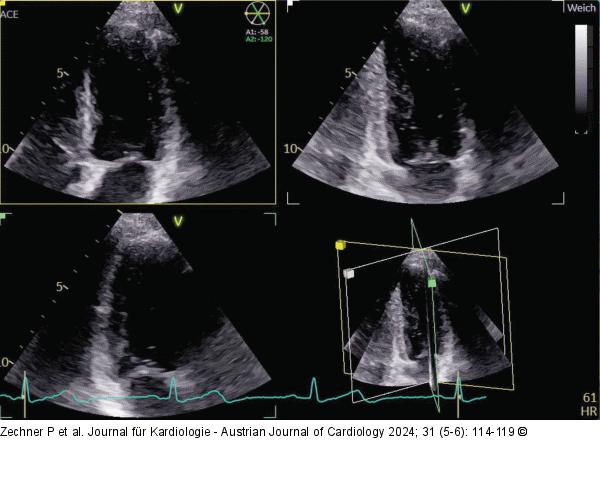

Abbildung 2: Echo (a): Untersuchung mit der Stabsonde von rechts parasternal, Patient liegt auf der rechten Seite; (b): Aortenklappenstenose mit Stabsonde von rechts parasternal. Die VTI von apikal betrug nur 80 cm, von parasternal mit der Stabsonde 103,5 cm, was einen gravierenden Unterschied bedeutet |

(a): Untersuchung mit der Stabsonde von rechts parasternal, Patient liegt auf der rechten Seite; (b): Aortenklappenstenose mit Stabsonde von rechts parasternal. Die VTI von apikal betrug nur 80 cm, von parasternal mit der Stabsonde 103,5 cm, was einen gravierenden Unterschied bedeutet |